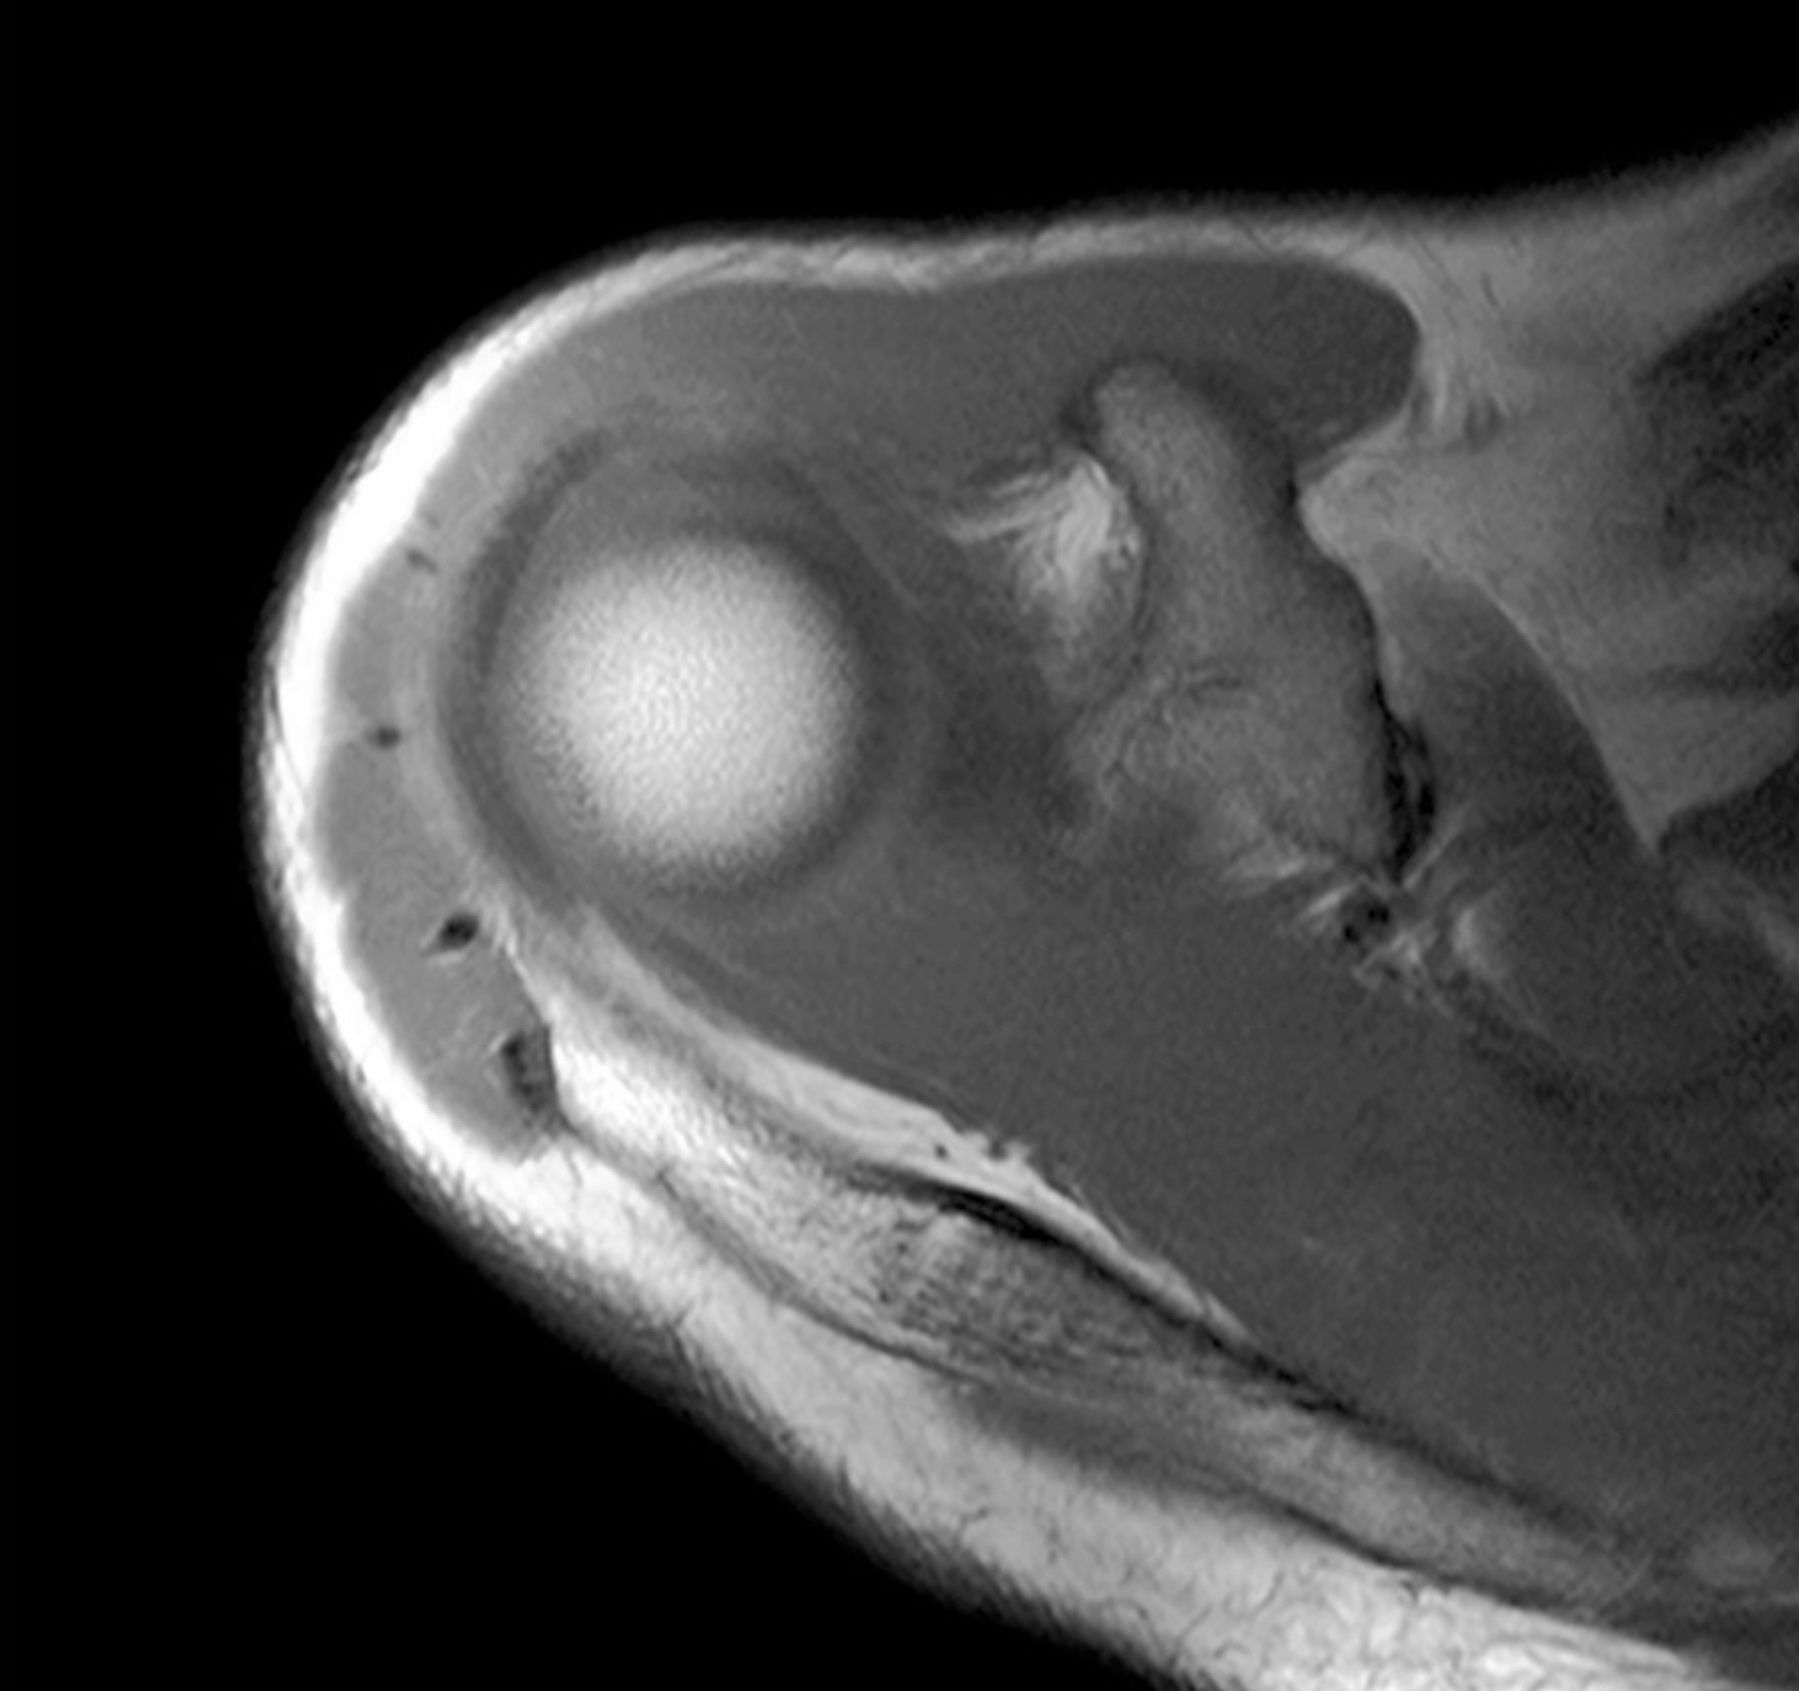

3. The elbow joint consists of three joints: the humeroradial, humeroulnar, and proximal radioulnar joints. Review the anatomy of the elbow joint. Include bones, articulations, ligaments, capsules, movements and limitations of movements. Relate the anatomy of the medial ulnar collateral ligament to Tommy John surgery.

5. The subacromial bursa does not normally communicate with the glenohumeral synovial joint cavity except in the case of a rotator cuff tear involving the supraspinatus muscle. (True)

7. A rupture of the tendon of origin for the long head of the biceps often injures the glenoid labrum. (True)